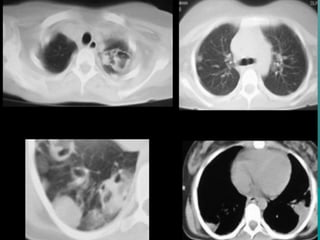

TEM EN TORAXTEM EN TORAX

Indicaciones para examen deIndicaciones para examen de

toraxtorax

Modo en espiral para estudios de rutina deModo en espiral para estudios de rutina de

torax v.g.torax v.g.

Neumonia, tumores, metástasis , linfomaNeumonia, tumores, metástasis , linfoma

anormalidades vasculares entre otrosanormalidades vasculares entre otros

FIBROSIS PULMONARFIBROSIS PULMONAR